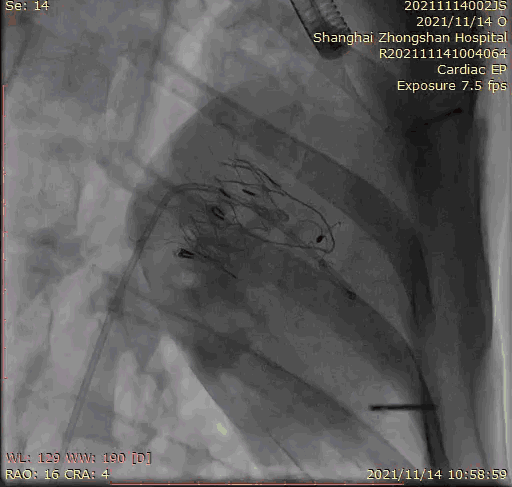

上海中山醫院葛均波院士、錢菊英院長、周達新教授、潘文志教授、潘翠珍教授、李偉教授共同完成此次臨床前研究。術后葛均波院士對Lux-Valve Plus的器械操作性能給予了高度評價,DSA和超聲影像也顯示出在本次研究中Lux-Valve Plus的安全性和有效性俱佳。

本次臨床前研究經右側頸靜脈置入LuX-Valve Plus輸送系統可調彎鞘管,在DSA及超聲引導下將人工三尖瓣瓣膜植入到原有三尖瓣位置,利用獨特的錨定技術將人工瓣膜支架可靠固定在預定的位置。

Lux-Valve是全球第一款具有我國完全自主知識產權的經導管介入三尖瓣置換系統,利用前瓣夾持及室間隔錨定的復合方式進行瓣膜裝置的固定,不依賴瓣環徑向支撐力,同時采用自適應復合裙邊材料,有效的貼合密封柔軟的三尖瓣瓣環,針對于三尖瓣返流的患者有優異的療效。Lux-Valve Plus采用全新的經血管輸送系統,經頸靜脈入路創傷更小,可以進一步降低手術風險。相信在后期正式臨床研究開展中,Lux-Valve Plus必定會為更多的三尖瓣反流患者帶來福音。